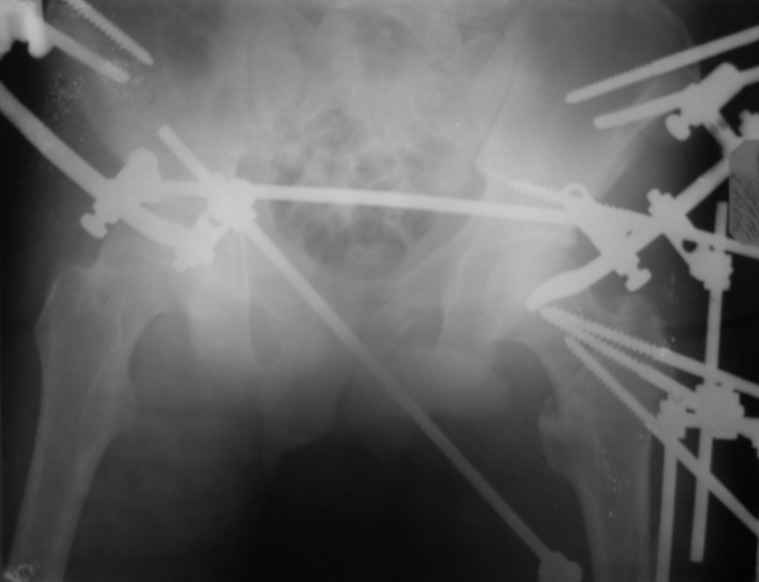

Вот снимки по свежей ситуации, парень 19 лет, длинный оскольчатый перелом бедра от шейки до в-с/3. давно уже ходит на своих ногах.

Делалось не мной (ассистировал), я на тазах "пока ещё не волшебник, а только учусь"

Представленные Вами рентгенограммы действительно являются примером качественной фиксации спице-стержневым аппаратом. Они, как ни что другое, многое иллюстрируют.

Кроме того, было бы ошибкой ставить знак равенства между нашим и Вашим пациентами. Они не только не похожи, разница между ними просто огромная. Говорю это не для того, чтобы задеть Вас или обидеть. Ни в коем случае. Просто теперь я понимаю, что Ваше мнением строится на простом преломлении Ваших подходов к лечению пациентов со свежими переломами, на ситуацию, абсолютно несопоставимую, подобную нашей.

Компоновку данного аппарата, в котором дистальный отломок фиксирован лишь на дистальном уровне, а проксимальный вообще сам по себе никак, только через бывший сустав, назвать стабильной никак нельзя. Нет стабильности - нет нормального заживления, но есть осложнения, надеюсь, это-то можно экстраполировать на вашего больного?